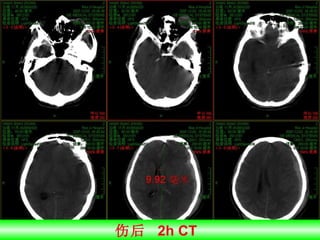

伤后  2h CT